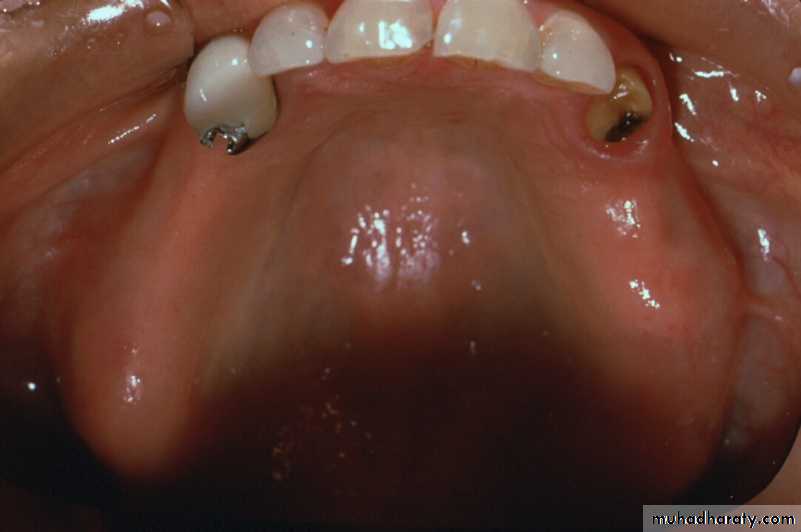

Extracoronal Attachments

• Positioned entirely outside the crown contour ; therefore, the normal tooth contour is maintained & the possibility of devitalizing a tooth is reduced in comparison to the intracoronal variety.

- Resilient variety is usually indicated in distal extension RPDs.ERA Extracoronal Resilient Semiprecision Attachment

- Due to versatility and robust design, extracoronal attachments are among the mostly commonly used attachments both in the precision and semi-precision varieties.UNFAVORABLE ATTACHMENT APPLICATIONCANTILEVERING EFFECT